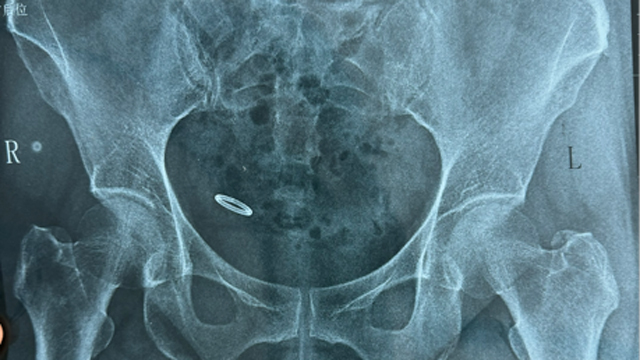

“肚子痛了好几天,怎么也没想到放了几十年的节育环会跑到腹腔里!”正处于手术后恢复阶段的钱女士心有余悸地说到:“感谢各位医生过硬的技术,这下终于可以放心了!”前不久,60岁的钱女士因下腹痛4天来来凤县人民医院就诊,门诊妇科彩超提示宫腔內未见节育器样强回声。行腹部X线提示盆腔内节育器,这可把钱女士吓坏了,这才想起36年前在当地医院上的环还没取呢!〔全文〕